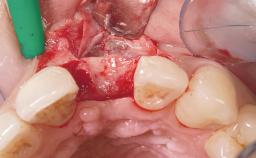

Immediate Flapless Placement of an Implant in a Maxillary Left Central Incisor Site

A 29-year-old female patient presented for treatment to replace the upper left central incisor tooth with an implant- supported restoration. The tooth had been intermittently symptomatic for the previous 12 months. The tooth had originally suffered trauma about 15 years previously. Several endodontic treatments had been performed, including an apicectomy procedure to retain the tooth. The patient was healthy and a non-smoker. She had reasonable expectations in regard to esthetic outcomes and the risk of marginal tissue recession following treatment. At medium smile, the gingival margins of the upper teeth were visible, with a display of 3 to 4 mm of the gingival margins. Gingival recession of tooth 21 and a discrepancy in the gingival levels between teeth 11 and 21 was observable during normal speech and smile.

| Placement Protocol | Immediate implant placement |

| Socket Integrity | Damage to one or more bone walls |

| Bone Volume | Damage to one or more socket walls |